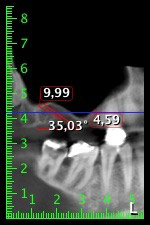

59-годишна пациентка с напреднал стадий на пародонтит описва неприятно чувство и лош вкус в първи квадрант в дисталната зона. Клиничният преглед разкрива силно уголемени пародонтални джобове и напреднала костна атрофия в зона 16 и 14. Рентгенографията потвърждава констатациите (Фиг. 1). Зъби 16 и 14 не могат да бъдат запазени.